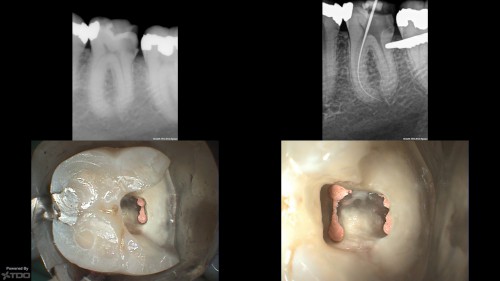

Non-vital Bleaching

By Dr. Angela Noguera / July 27, 2018

Tough very old discolored tooth. Previous RCT dome over 40 years ago. No pain, completely […]